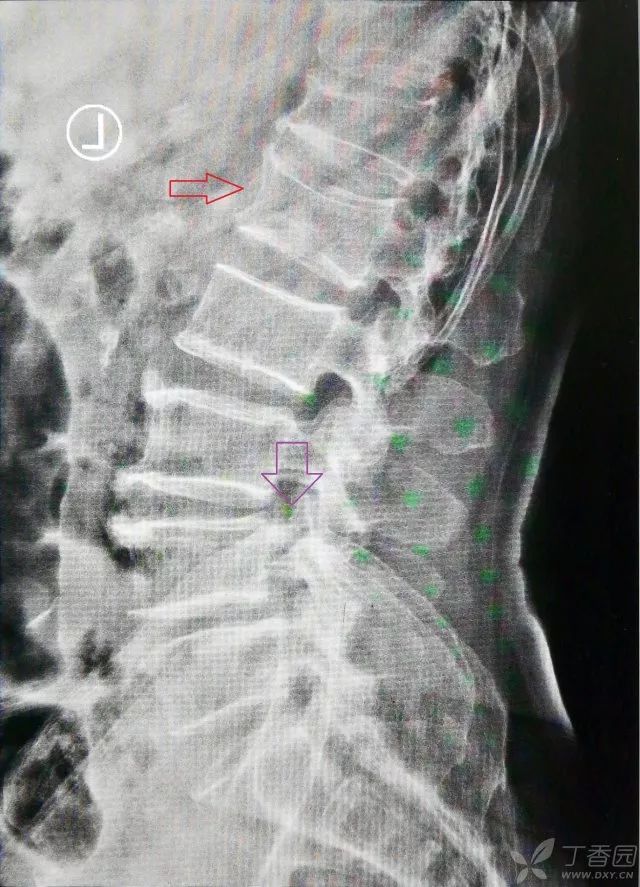

以这个病例为例,核磁上看到的责任椎在侧位 X 线上对应的,很容易找到(红色箭头),再看侧位片髂脊高点的位置(紫色箭头)。然后再到正位 X 线片上从髂脊高点位置开始数,这样就可以完全排除各种变异带来的干扰。

下面这张侧位 X 线片看,责任椎是髂脊高点上第三个椎体。那么回到正位片,我们同样也从正位片的髂脊高点往上数三个椎体,就一定是责任椎体。

一句话总结:CT 核磁不会出错,而脊柱侧位片一定是和 CT 核磁对应的,从椎间隙开始数一定没问题,顺序:CT 核磁——脊柱侧位片——脊柱正位片(通过髂嵴最高点判断)。